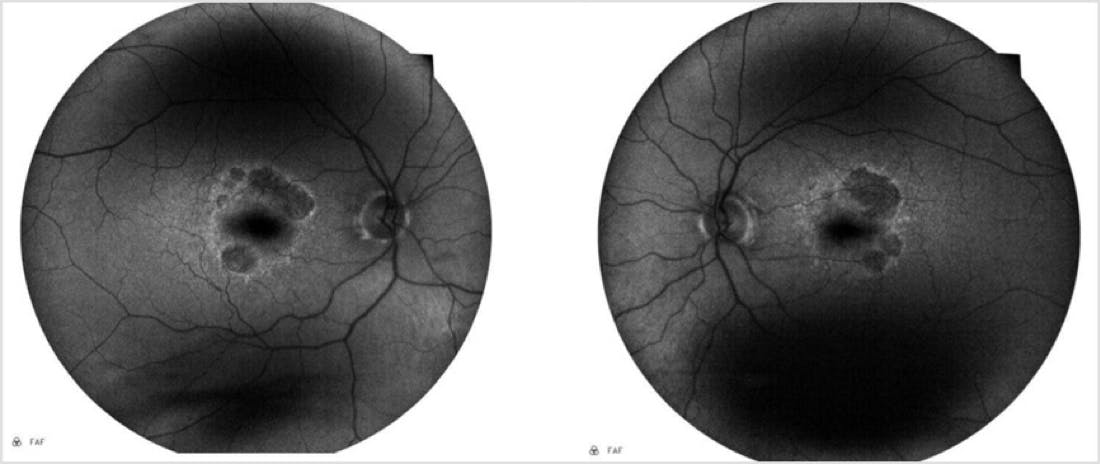

The patient presented back in my clinic approximately 6 months after the initial consultation. He noted persistent symptoms of difficulty with reading and using the computer but denied any significant worsening since the last visit. His BCVA was 20/25 OD and OS. Anterior segment examination revealed well centered posterior chamber IOLs with trace posterior capsular fibrosis in both eyes. His clinical examination was unchanged. Careful review of his retinal imaging revealed progression of the hypoautofluorescent lesions on FAF (Figure 4). OCT revealed worsening choroidal hypertransmission defects OS>OD with no evidence of exudation (Figure 5).

This case is notable for several reasons. First, it shows the utility of multimodal imaging, and in particular, the use of FAF imaging for monitoring patients with GA. Note that in Figure 1, it is difficult to appreciate the borders of the GA lesion, whereas in Figure 2, clearly evident are hypoautofluorescent areas (indicating areas of already dead retinal pigment epithelium) and hyperautofluorescent areas (indicating areas of potential expansion of the GA lesion). Meanwhile, the OCT image in Figure 3 helped support the diagnosis of GA while also demonstrating key signs of potential progression. With the benefit of serial imaging captured at the follow-up visit (Figure 5), it was possible to detect progression of this patient’s GA despite stable visual acuity and no change on clinical examination.